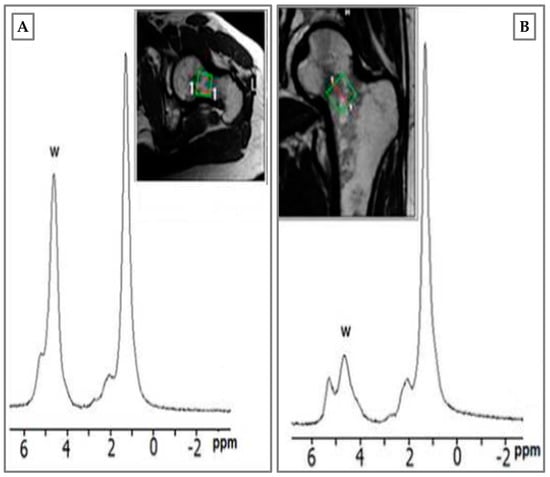

- Di Pietro, G.; Capuani, S.; Manenti, G.; Vinicola, V.; Fusco, A.; Baldi, J.; Scimeca, M.; Hagberg, G.; Bozzali, M.; Simonetti, G.; et al. Bone Marrow Lipid Profiles from Peripheral Skeleton as Potential Biomarkers for Osteoporosis: A 1H-MR Spectroscopy Study. Acad. Radiol. 2016, 23, 273–283. [Google Scholar] [CrossRef]